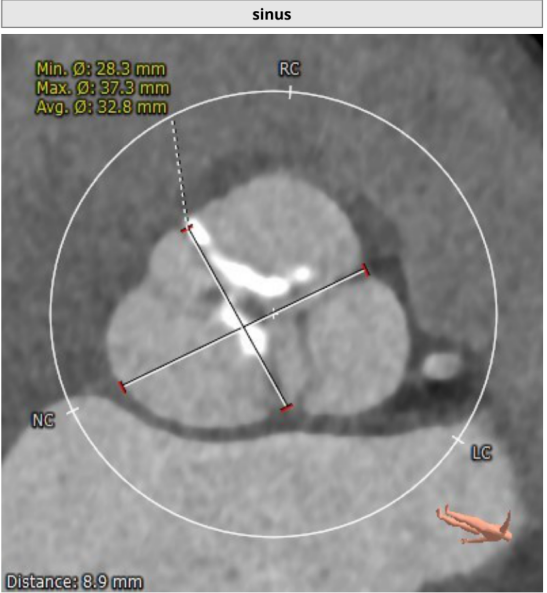

患者主动脉根部、冠状动脉、主动脉增强CT扫描,通过专业评估软件分析提示该患者主动脉瓣为功能型二叶瓣、中度钙化,左右冠窦可见融合、瓦氏窦结构较大,左右冠开口高度尚可,升主动脉最宽处约42.9mm,左室明显扩大。主动脉瓣环平均径约26.3mm,流出道平均径约27.5mm,STJ平均径约34.3mm,双侧股动脉直径均大于6mm。冠脉见钙化灶,钙化积分总和为1590.2;冠脉CTA提示:“左主干、三支冠状动脉粥样硬化改变,局部管腔可见40~60%狭窄”。

窦部:32.8mm